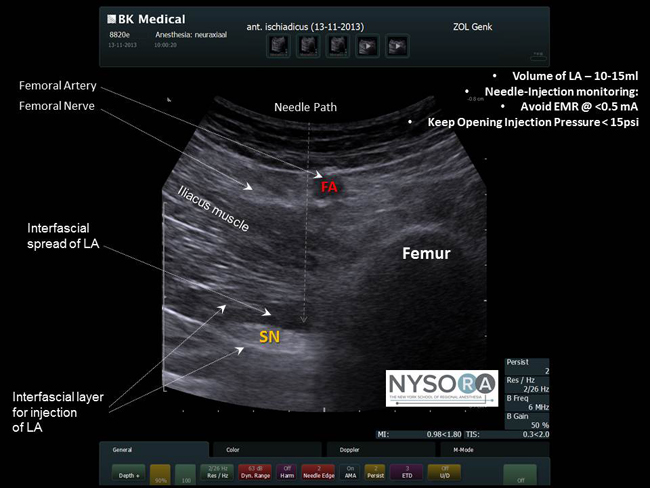

Featured Education Video - Ultrasound-Guided Femoral Nerve Block |

Needle and Injection Monitoring During Nerve Block Placement Sponsored by Macosta Medical USA |